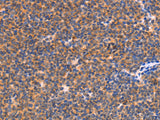

Applications IHC

IHC 1:25-1:100